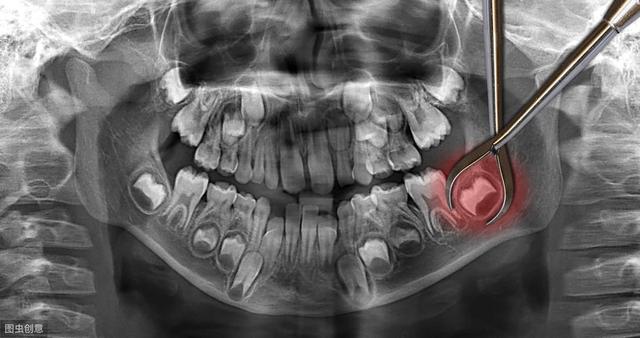

这种情况下,尽早拔掉阻生智齿就是免除后顾之忧最好的选择。甚至我们在条件允许的情况下趁早下手,可以提前拔除智齿的牙胚,不让它有萌出和干扰其他牙齿的机会。现在检查智齿都会拍X全景片,片里可以清楚地看到有没有智齿牙胚,如果没有太大风险的(比如牙胚位于下颌神经管内),我们都可以在智齿萌出之前,选择合适的时机进行开窗拔除牙胚,不让它有作乱的机会。

至于很多朋友害怕的拔智齿会很疼,其实大可不必担心。拔阻生智齿可能有点麻烦,但也没有大家想象中的那么恐怖。医生会根据拔牙的难易程度选择局麻或全麻。局麻的话,注射了麻醉剂后,你的嘴巴就麻木了。而全麻就更舒服了,等你醒过来,智齿已经没了。